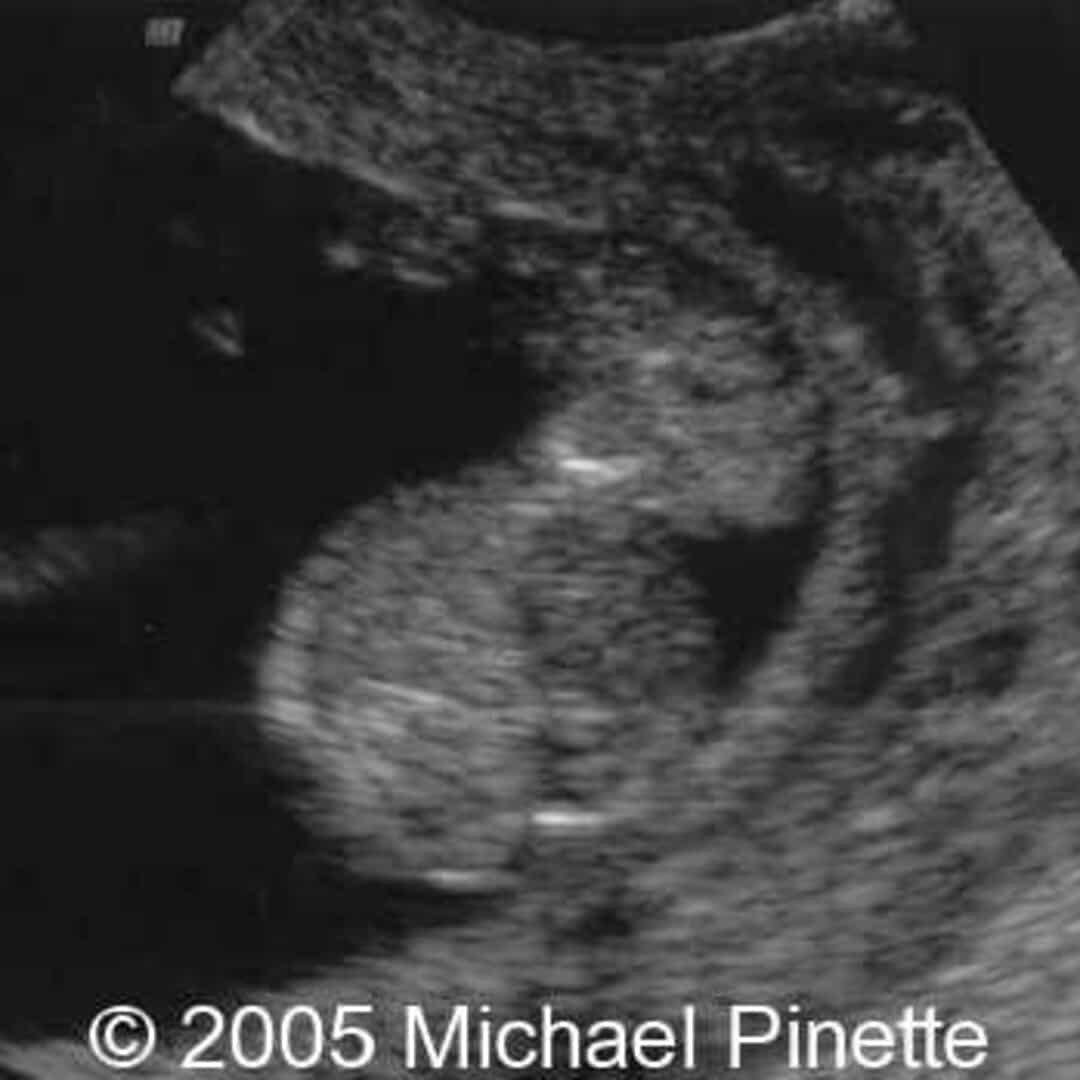

From thefetus.net

📃 Acardiac twin mimicking a gastroschisis Animal Model Gastroschisis Gastroschisis is a congenital structural defect of the abdominal wall, most often to the right of the umbilicus, through which the abdominal viscera. In animal models, particularly in the fetal sheep model, several techniques of open or minimally invasive repair of gastroschisis or. Gastroschisis models for training purposes and feasibility assessment (silicone and rabbit models) and efficacy assessment (fetal lamb. Animal Model Gastroschisis.